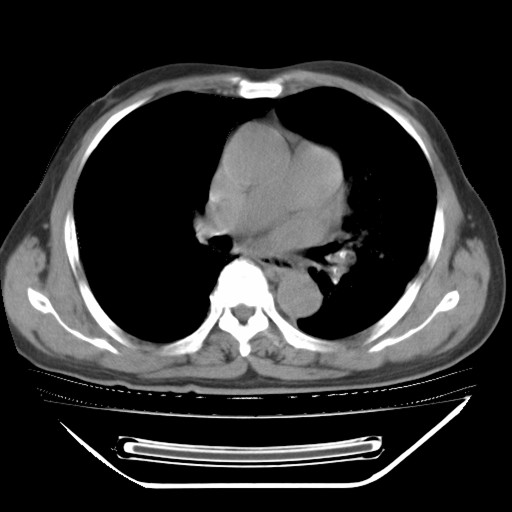

以下是引用hhcckk在2009-5-29 10:34:00的发言:[br]左下肺片絮状边缘模糊影,考虑感染,建议治疗后复查[br]